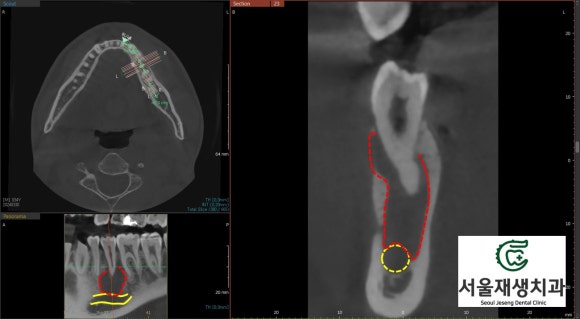

CT의 도움이 필요한 순간!

![[치외치신경치료] 뿌리 끝 염증이 커서 발치해야된대요! 치아 머리에 볼~록! 알고보면 무서운 작은 혹 (서울재생치과) 관련 이미지 13](https://pub-9f2bb3498faf4d1d8714b41df24753e3.r2.dev/content/clinics/archive/nqmm0udu86/naver_blog/honeybeevuvu/assets/by_hash/7982d46f8392fd0a45b45ff83820f0c5cfe012543d06151e9e8c3ed314e6f903.jpg)

U자형의 잇몸뼈 내부가

텅~텅 비어있습니다.

광범위한 염증 때문에

뼈가 모두 녹아버렸군요.

![[치외치신경치료] 뿌리 끝 염증이 커서 발치해야된대요! 치아 머리에 볼~록! 알고보면 무서운 작은 혹 (서울재생치과) 관련 이미지 14](https://pub-9f2bb3498faf4d1d8714b41df24753e3.r2.dev/content/clinics/archive/nqmm0udu86/naver_blog/honeybeevuvu/assets/by_hash/f698ab08a769f77f70e1ab2e4b7243c4a5a755c566e6d8d8e637096050cf8d32.jpg)

내부의 뼈가 다 녹은 것도 모자라

단단한 테두리뼈도 일부 녹이고 있습니다.

그 결과,

잇몸쪽으로 불거져나오는

잇몸염증이 발생하게 되었습니다.

![[치외치신경치료] 뿌리 끝 염증이 커서 발치해야된대요! 치아 머리에 볼~록! 알고보면 무서운 작은 혹 (서울재생치과) 관련 이미지 15](https://pub-9f2bb3498faf4d1d8714b41df24753e3.r2.dev/content/clinics/archive/nqmm0udu86/naver_blog/honeybeevuvu/assets/by_hash/d4e0dece32d30b1b6ab0b453c776a0a04ffa7773279134518fb6282492056c5c.jpg)

더군다나, 염증의 하방에는

턱을 지나가는 가장 큰 신경인

'하치조신경관'이 있어,

언제라도 '감각이상'이 일어날 수 있는

상황이었죠.

조금만 더 늦었어도 큰 일 나실 뻔 했습니다.